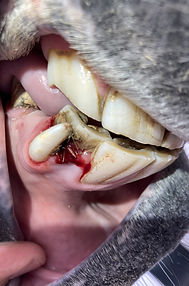

DENTISTERIA

A dentição dos cavalos reveste-se de especial importância não só no que toca a boa digestão como também na boa forma física e boa condução do cavalo. Normalmente dever ser feito um check-up cada ano de modo a corrigir os problemas que surgem. Tratamos de enviar o relatório de todas as intervenções e relembramos quando tem de ser feita nova consulta.